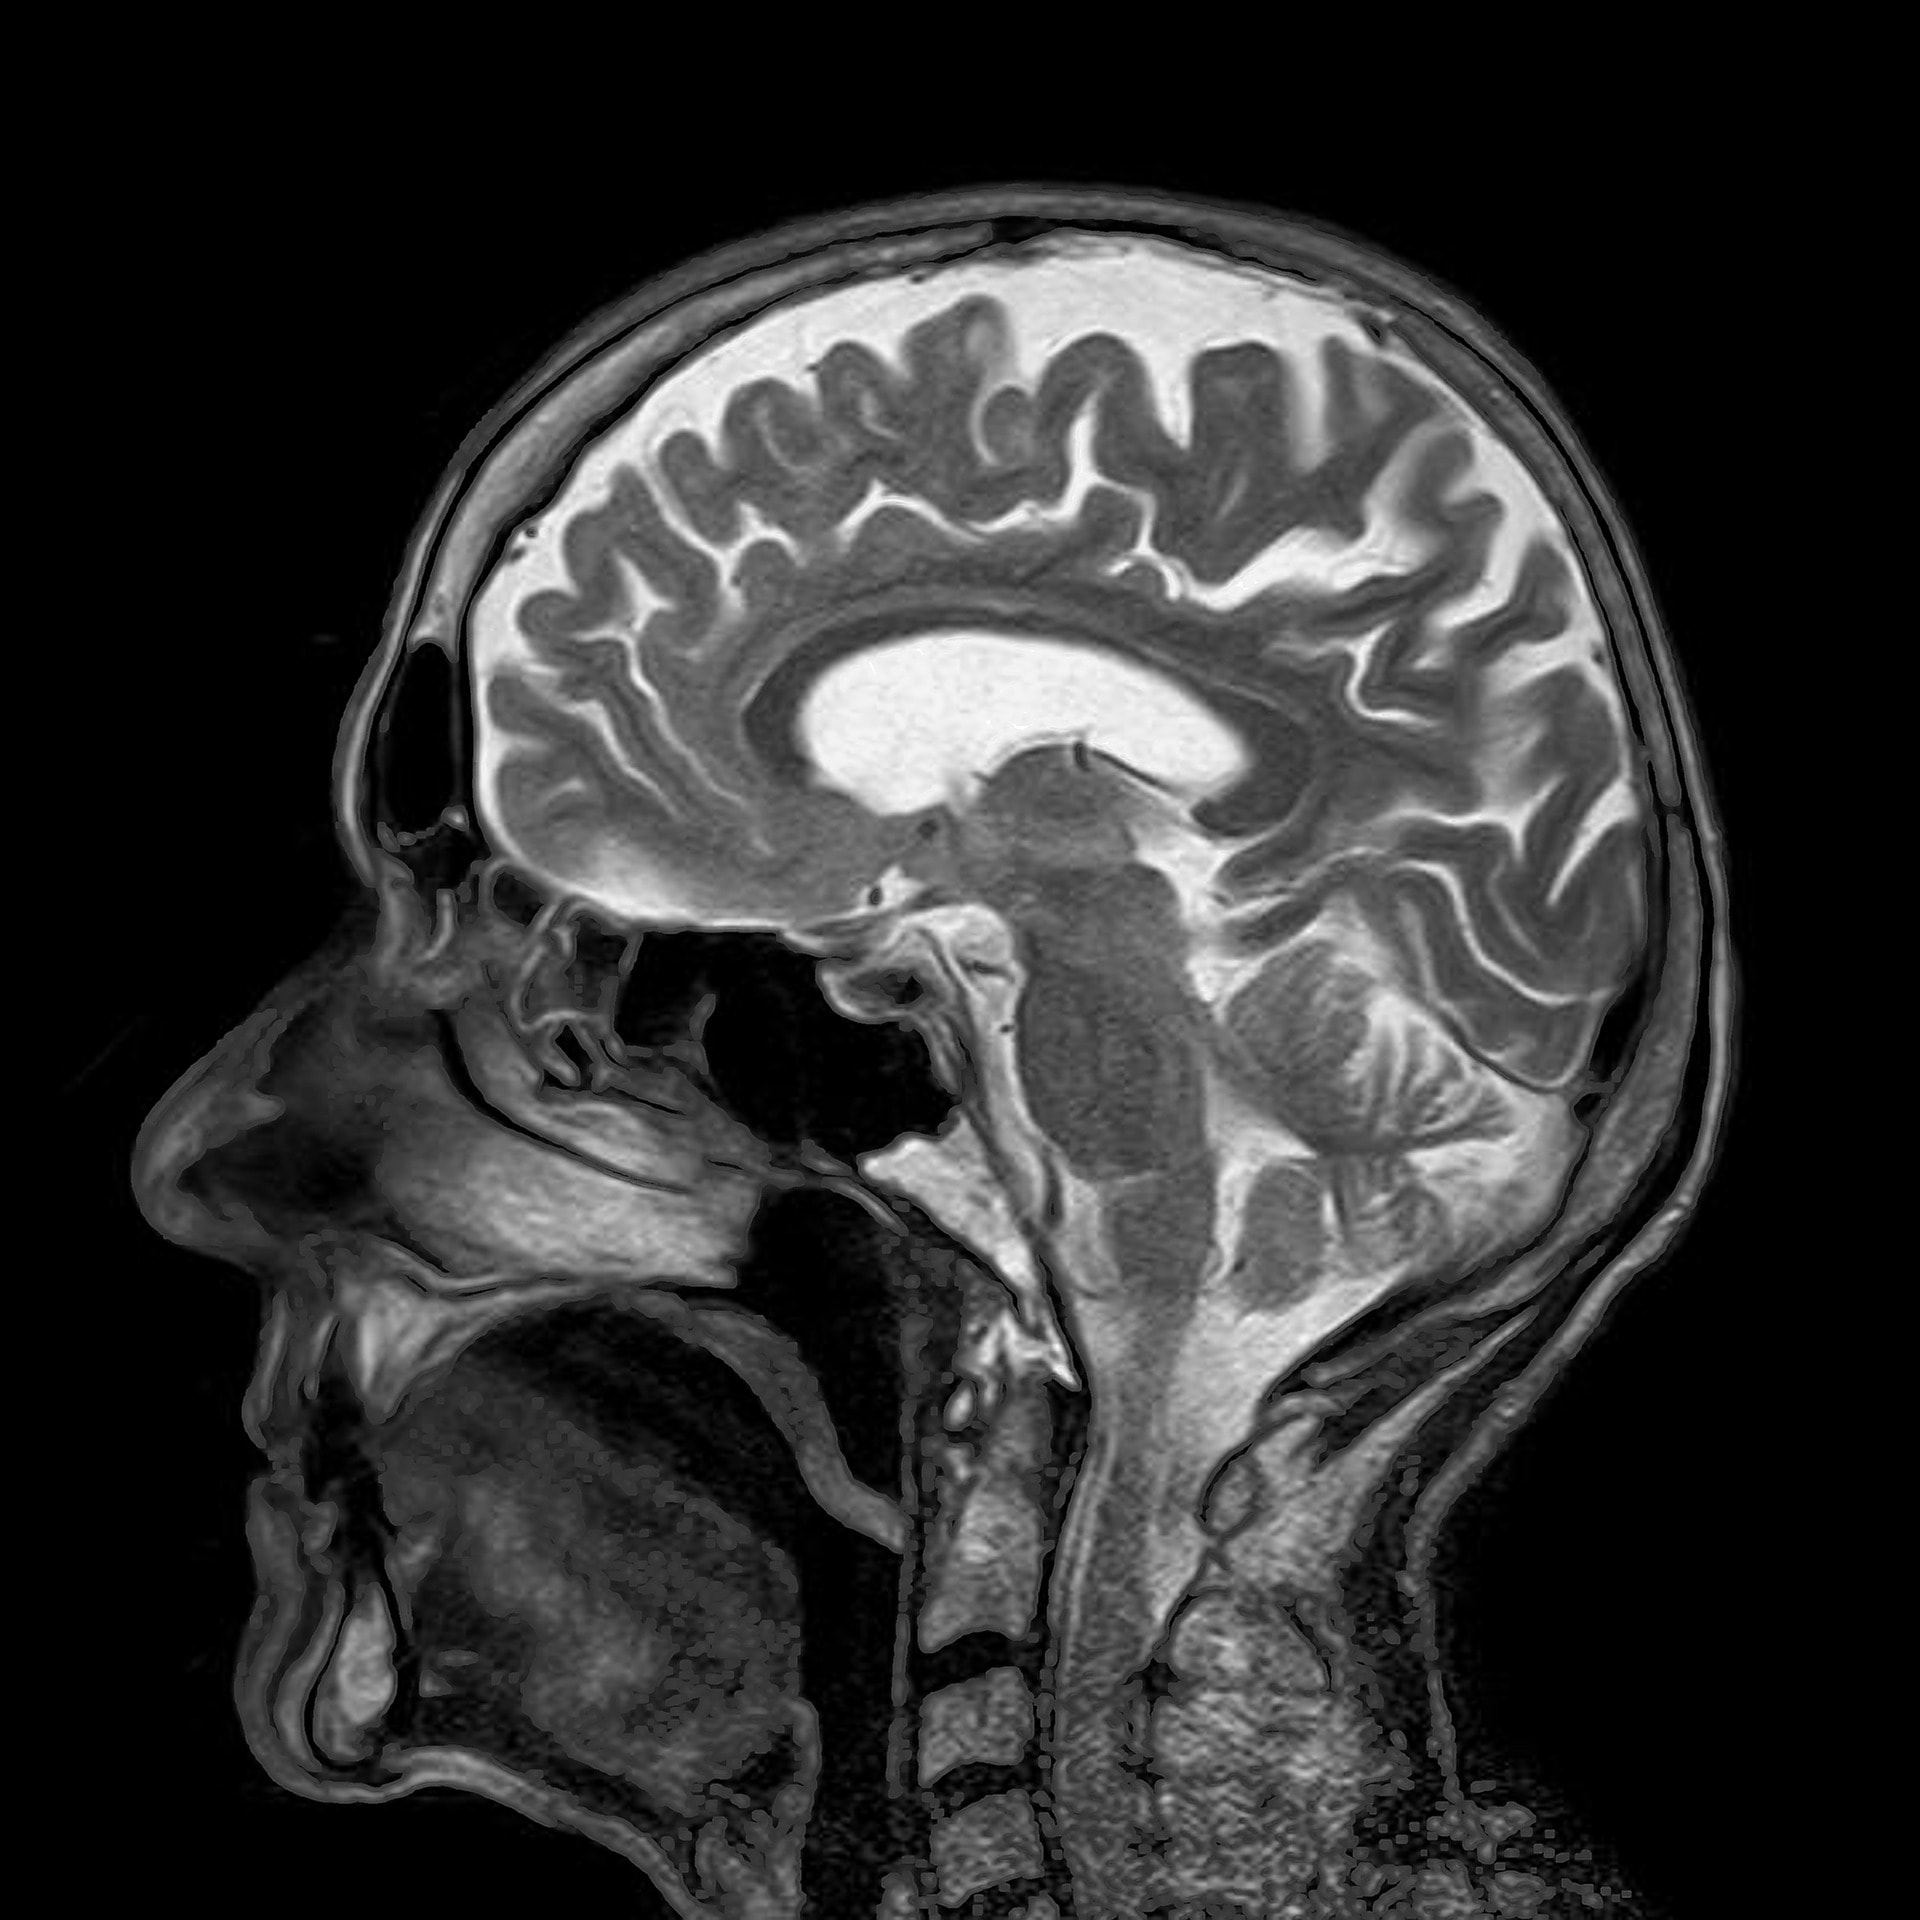

Magnetic resonance imaging (MRI) merupakan satu teknologi pengimejan yang menggunakan magnet dan gelombang radio untuk menunjukkan dan merakamkan sesuatu struktur anatomi dengan lebih jelas.

- Menghasilkan imej yang mempunyai kontras tisu lembut yang tinggi dengan keratan resolusi yang lebih baik jika di bandingkan dengan x-ray dan CT scan.

- Membenarkan imej dibuat dalam berbagai keratan seperti sagital, koronal, oblik, transvers atau aksial tanpa perlu mengubah kedudukan pesakit.